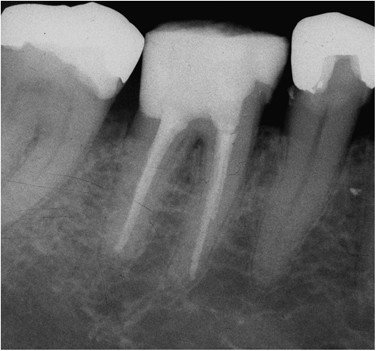

3. Evaluate the root canal treatment of tooth # 1.7?